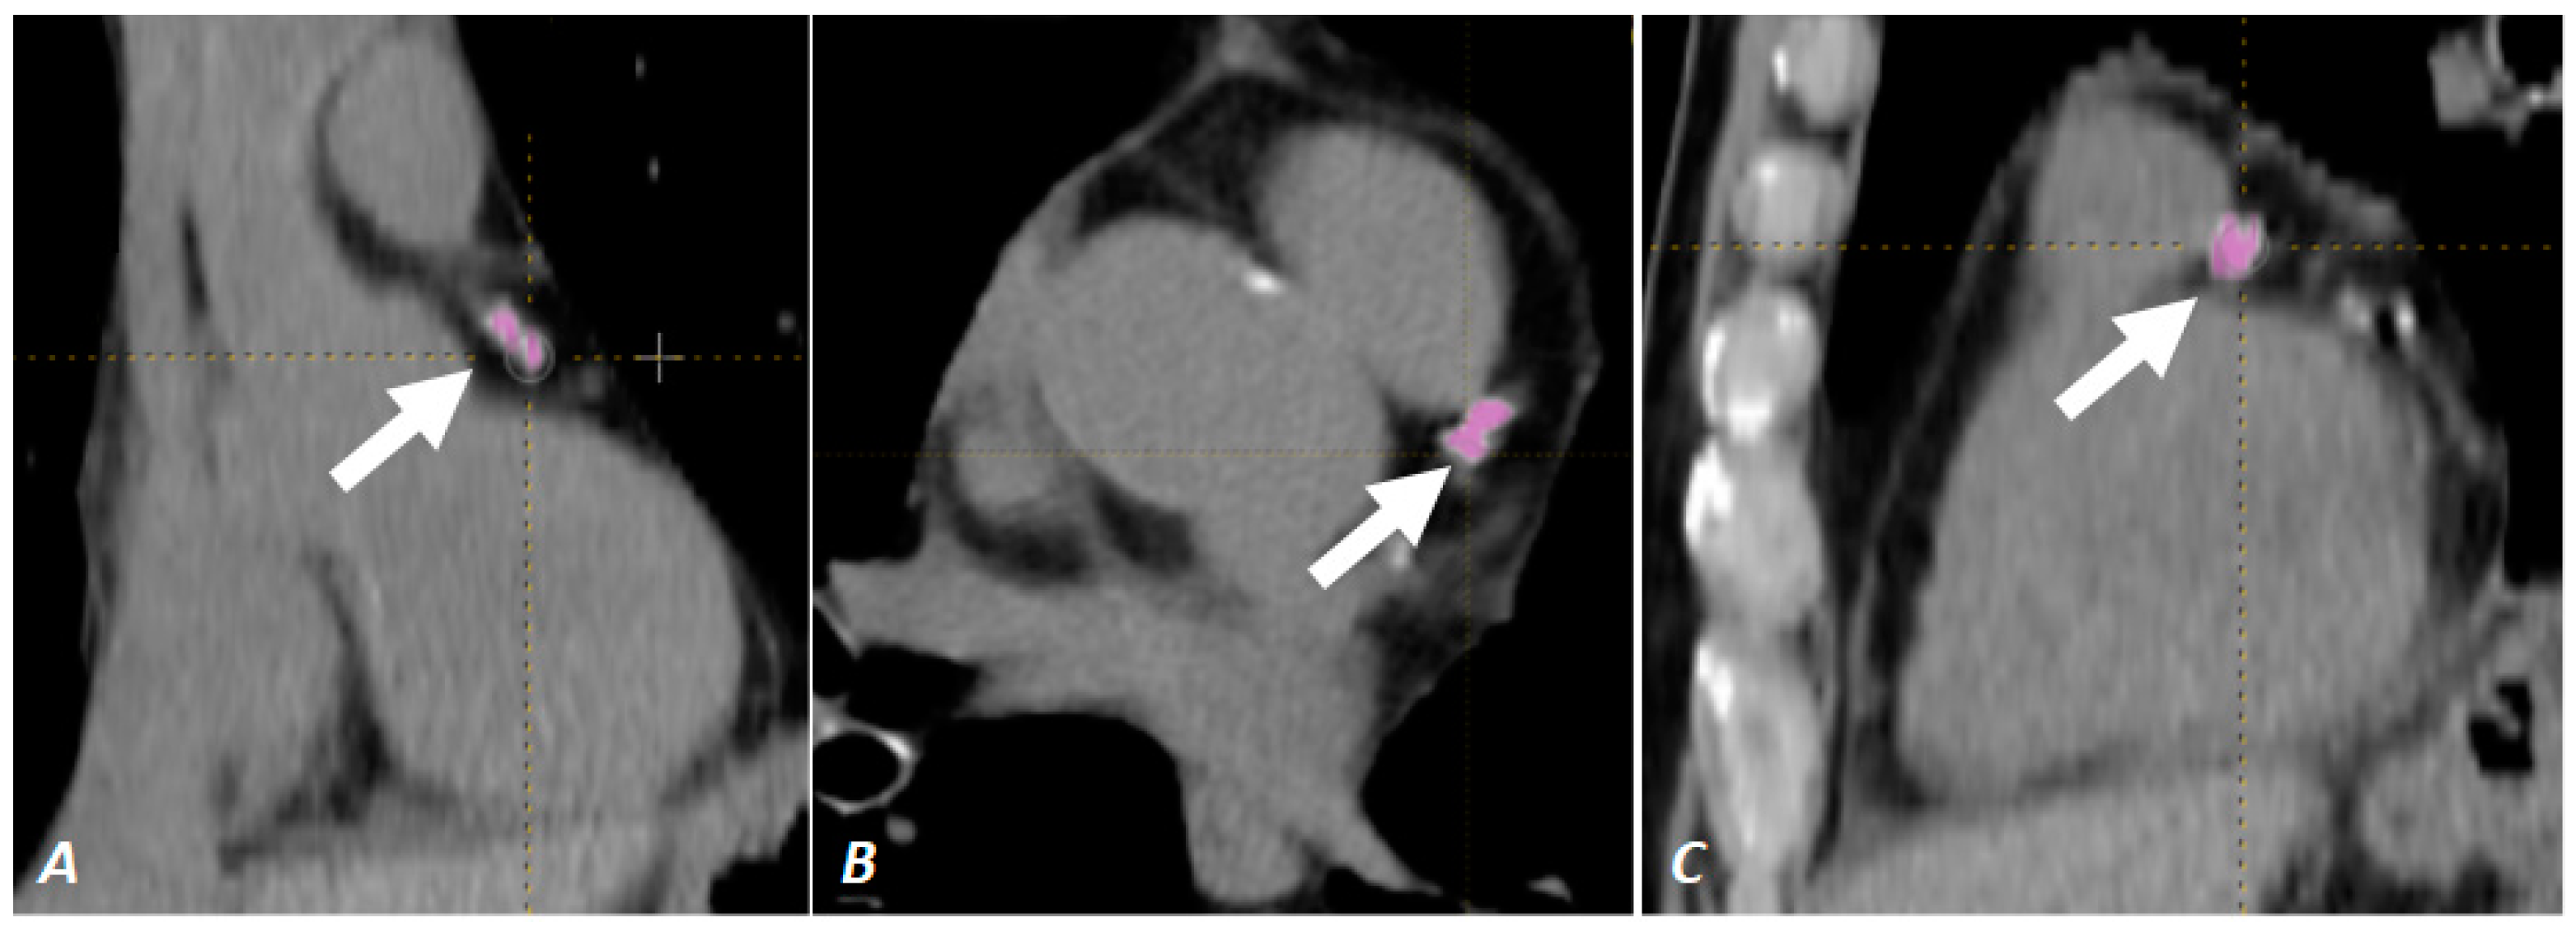

2.4. CAC Score Calculation

- Nardone, V.; Reginelli, A.; De Marco, G.; Di Pietro, T.; Grassi, R.; Corte, C.M.D.; Fasano, M.; Ciammella, P.; Vicidomini, G.; Morgillo, F.; et al. The role of coronary artery calcification score in lung cancer patients. Eur. J. Radiol. 2022, 147, 110140. [Google Scholar] [CrossRef]